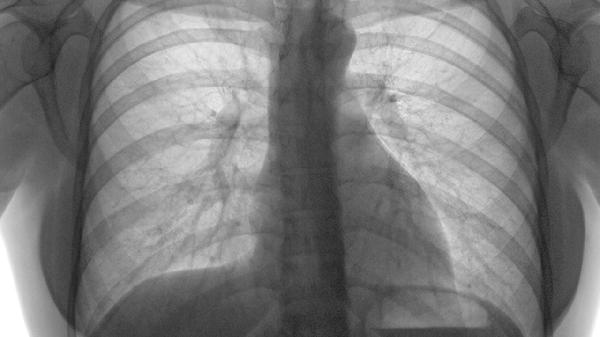

肺栓塞的肺部CT血管造影CTA影像主要通过显示肺动脉内的血栓来诊断。肺栓塞的CTA影像特征主要包括肺动脉充盈缺损、肺动脉扩张、肺实质灌注异常、右心室增大及肺动脉高压。

肺实质灌注异常是肺栓塞的间接征象,通常表现为肺野内的低密度区域,与正常灌注区域形成对比。CTA影像中,灌注异常区域可能呈楔形或不规则形,通常位于肺外周。灌注异常的范围和程度反映了血栓对肺血流的影响,有助于评估肺栓塞的严重程度。